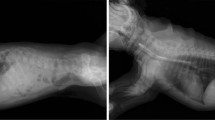

This study was conducted in accordance with the guidelines of the North Carolina State University Institutional Animal Care and Use Committee (IACUC, 17-168-0). Ten adult dogs of each of the following five breeds were selected for evaluation including Yorkshire Terrier, Miniature Poodle, Miniature Schnauzer, Dachshund, and Cavalier King Charles Spaniels. These breeds were selected due to the reported increased occurrence in these breeds (Borgarelli and Buchanan 2012; Han et al. 2013). Dogs were evaluated by a board certified veterinary cardiologist or a cardiology resident under the supervision of a boarded cardiologist at North Carolina State University College of Veterinary Medicine. Dogs diagnosed with a systolic left apical heart murmur and had echocardiographic findings consistent with mitral valve disease (valve thickening, prolapse, and/or mitral regurgitation) were selected for DNA collection (Borgarelli and Haggstrom 2010).

No high, moderate, low or modifier impact variants were found in all 50 dogs. (Fig. 1) One high impact variant (BTNL10, Chr14:507272) was found in ten of ten Yorkshire Terriers, one high impact variant was found in ten of ten Miniature schnauzers (GLYAT, Chr18: 37676090), and one was found in ten of ten CKCS (MFSD13A, Chr6:23283876). No high impact variants were found in all ten Dachshunds or Miniature Poodles. No moderate impact variants were found in all ten Yorkshire Terriers or Miniature Poodles. Four moderate impact variants were found in all ten Schnauzers, one was found in Dachshunds and nine in CKCS (Supplemental Table 4). All of these were only found in these breeds and all but one of these (Chr12:36801705, COL12A1) were in genes that did not have any evident pathophysiological link to valve disease. The one variant in the CKCS in a gene with an association with the heart valve, COL12A1, was subsequently only found in 84 of 100 affected CKCS.